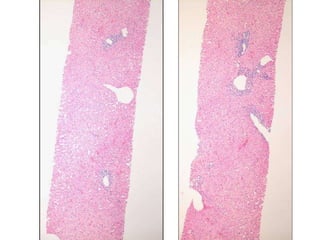

BS09-22346 49 yo, female.  Clinical history:  Acute hepatitis.  Mild elevation of IgG, ANA.  Viral serologies negative.  No drug/toxin exposure history.  AIH?

BS09-10453:  Dx: Chronic hepatitis, with severe activity (perivenular confluent necrosis) and focal fibrous septa, compatible with autoimmune hepatitis. Corresponds to: Modified Ishak stage 2/4 Metavir F2

BS09-22346 49 yo,female. Clinical history: Acute hepatitis. Mild elevation of IgG, ANA. Viral serologies negative. No drug/toxin exposure history. AIH?

BS09-10453: Dx:Chronic hepatitis, with severe activity (perivenular confluent necrosis) and focal fibrous septa, compatible with autoimmune hepatitis. Corresponds to: Modified Ishak stage 2/4 Metavir F2

LS08-10290 Abnormal LFT, negative for Hepatitis A, B, C.  Sono: heterogeneous liver.

BS09-10453:  Dx: Chronic hepatitis, with severe activity (focal parenchymal collapse) and cirrhosis, suggestive of autoimmune hepatitis. Corresponds to: Modified Ishak stage 4/4 Metavir F4

LS08-10290 Abnormal LFT,negative for Hepatitis A, B, C. Sono: heterogeneous liver.

BS09-10453: Dx:Chronic hepatitis, with severe activity (focal parenchymal collapse) and cirrhosis, suggestive of autoimmune hepatitis. Corresponds to: Modified Ishak stage 4/4 Metavir F4